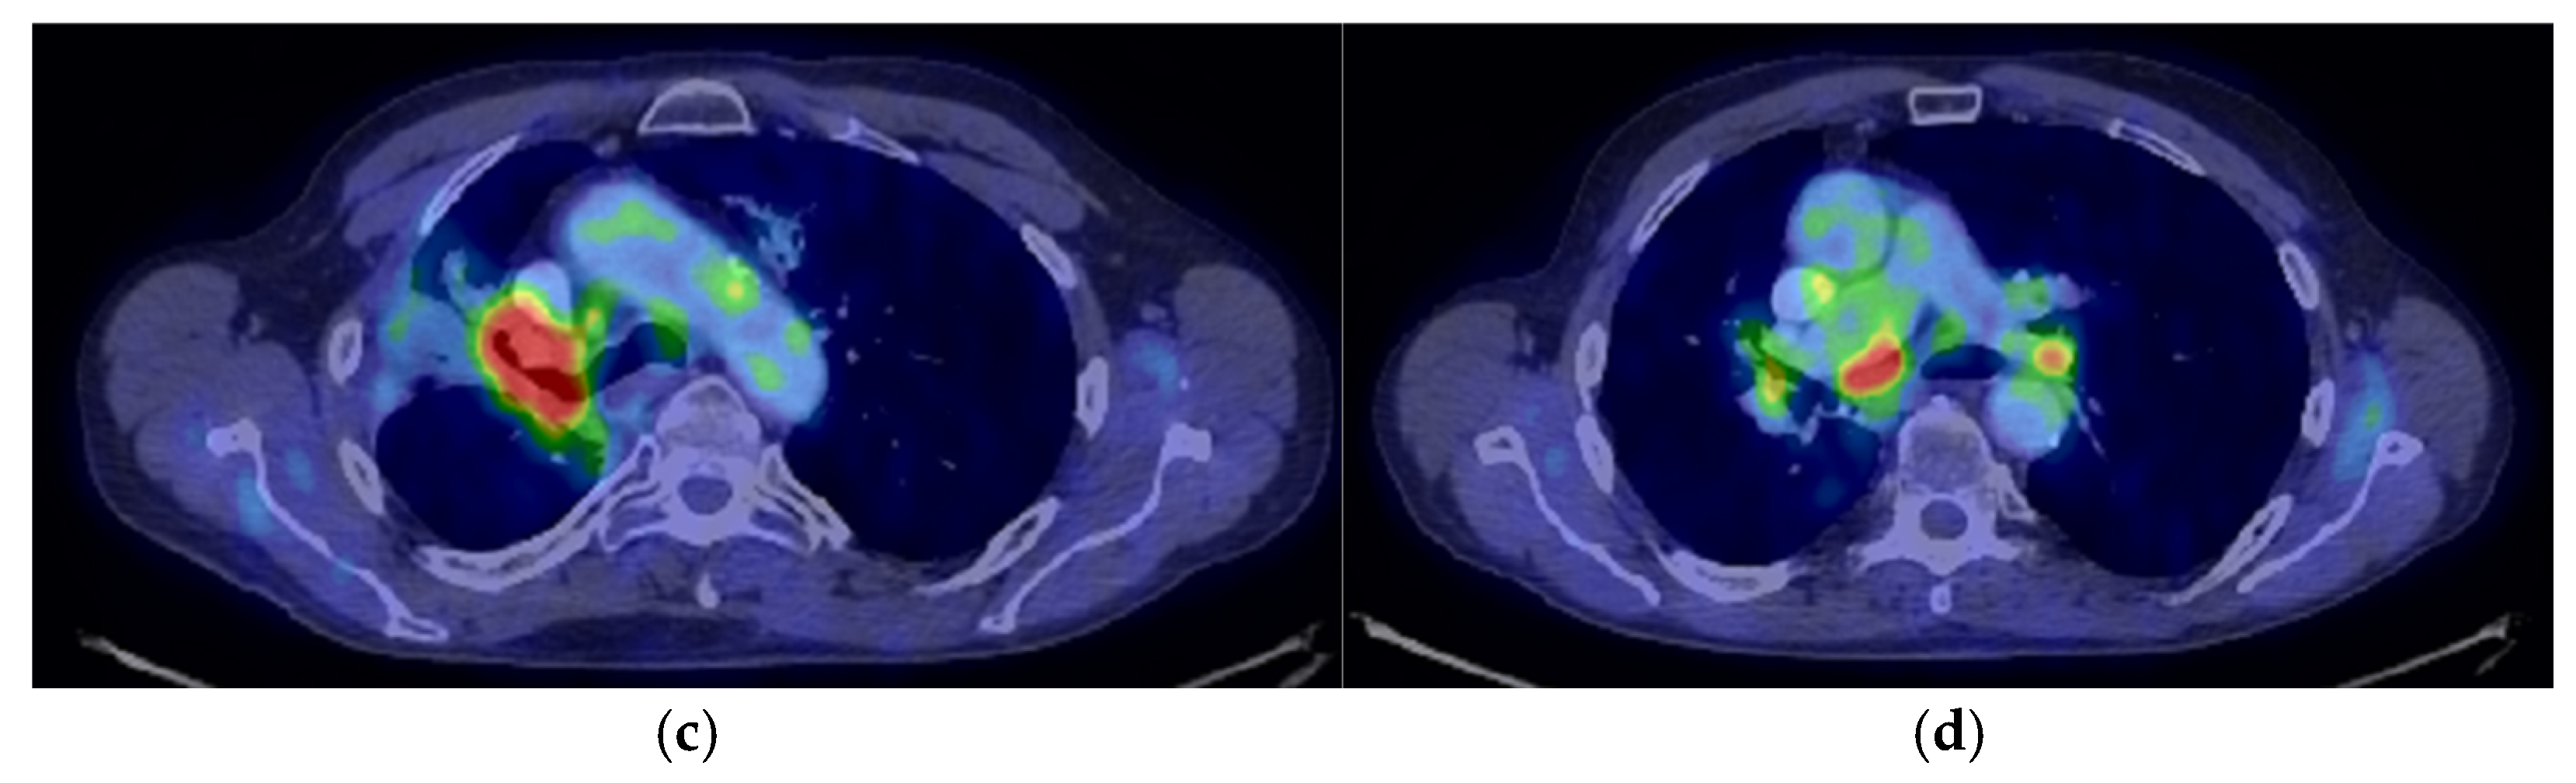

2. Case Presentation

2.2. Monitoring 2022: Oncological Commission 1910/16.08.2022

2.3. Oncological Committee 07/25/2023 Recommended

- Consider rescue re-irradiation (SBRT), taking into account the current primary tumor dimensions of 24 × 34.2 mm on PET CT from 06/2023 and also the total dose previously administered (08–09/2020), the previously applied fractionation, the time between the two irradiations, the cellular repair time and the dose constraints for the organs at risk.

3. Case Results